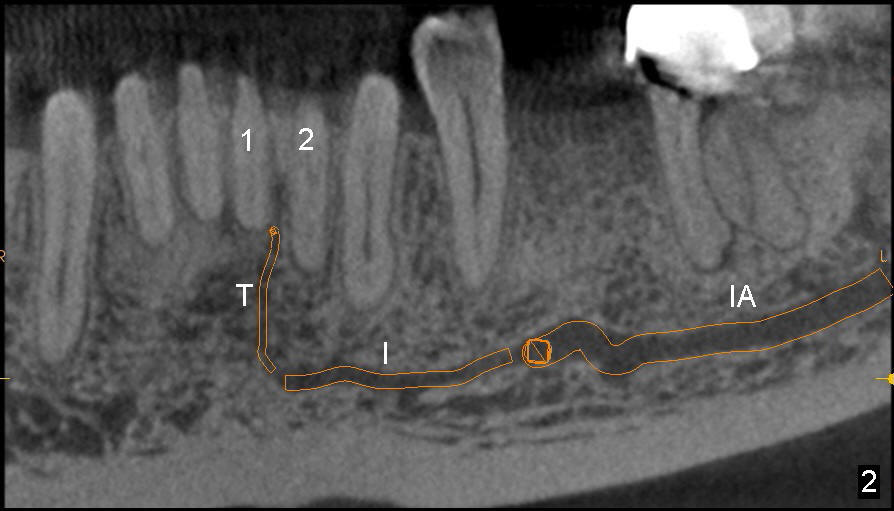

The incisive canal (Fig.1,2: I) is the anterior extension of the inferior alveolar canal (IA) after the latter gives rise to the mental nerve (circle). The terminal segment of the incisive canal (T or arrowheads in Fig.1) is located between the lower central (1) and lateral (2) incisors (3: lower canine).

After extraction of the central (Fig.3 black area), osteotomy for an immediate implant (Fig.4 white outline) should have a chance to violate the integrity of the terminal segment of the incisive canal, causing hemorrhage. Once the implant is placed, the hemorrhage should be able to stop.